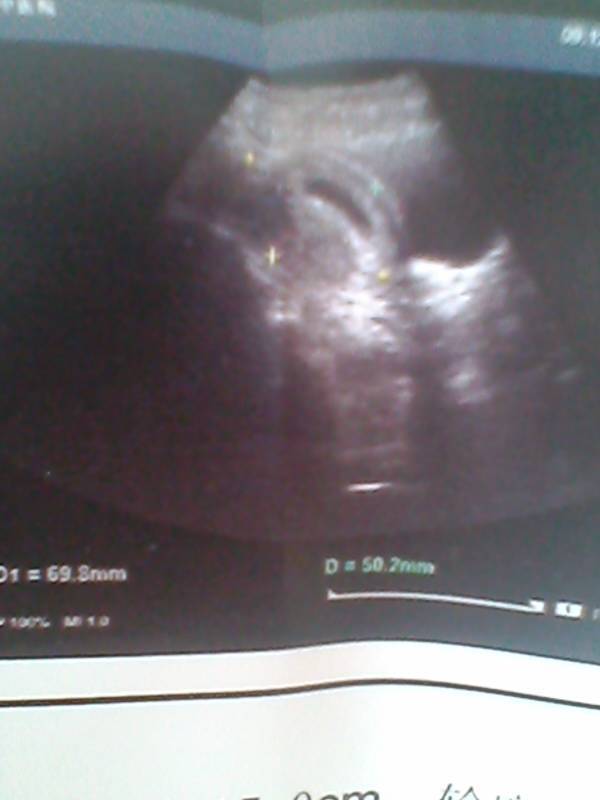

看我的宝宝,还这么小,好希望快点长大啊! 看我的宝宝,还这么小,好希望快点长大啊!😊 点击展开 爱^ω^等待 2015-04-20 15:35 为您推荐: 其他回答 很快的!,, 水墨青花! 2015-04-20 18:15 这个拍的好清楚 好孕,羊宝宝么么哒 2015-04-20 17:05 哦!那我就不懂了,祝好孕 小小杨De娘* 2015-04-20 16:28 祝你好孕。 怪兽别跑!biubiubiu_BgQ3 2015-04-20 16:17 后期长得很快的。 ヤ爱哭dē小魔女 2015-04-20 16:12 加载更多 相关问题 多希望娃儿能快点长大 男朋友一直把我当小孩一样,每次吵架的时候都说希望我快点长大 他是真心爱我吗? 真希望宝贝快点长大啊!折磨人啊!⊙﹏⊙